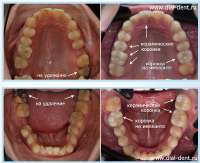

16953018548481.png 364Кб, 600x800

600x800

16973002837440.png 150Кб, 565x414

565x414

16988896475040.png 45Кб, 287x200

287x200

16968953426140.png 1563Кб, 1665x1250

1665x1250